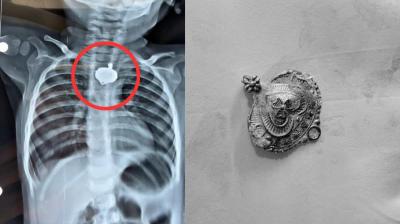

बड़वानी में 9 माह के बच्चे की आहार नली में फंसा मंगलसूत्र, डेढ़ महीने बाद एक्स-रे से खुलासा

24 Nov, 2025 08:30 AM IST | AVSNEWS.COM

बड़वानी: रविवार को जिला अस्पताल में एक बेहद संवेदनशील और हैरान करने वाला मामला सामने आया. जब 9 माह के एक बच्चे के गले में मंगलसूत्र फंसा हुआ देखा गया. घटना...